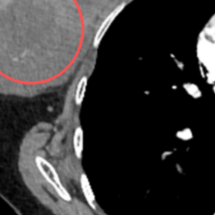

患者谢某(化名)一年前无意中触摸到右侧乳房有一小肿块,因不痛不痒,便未予重视。然而近三个月来,肿块迅速增大,就诊时已长成直径约10厘米,导致乳房严重变形,生活深受影响。来到郴州市第四人民医院心胸乳腺外科就诊,经过紧急穿刺活检,确诊为“乳腺叶状肿瘤”。

直径约10厘米的肿块。

由于肿瘤体积巨大,几乎替代了正常腺体,且表面皮肤已出现水肿,为彻底切除病灶、避免复发,医疗团队经慎重评估,为患者施行了右侧乳房全切术。术后病理证实为交界性叶状肿瘤,切缘干净。目前患者恢复良好,已康复出院。她追悔道:“总以为不疼就没事,要是早一年来筛查,结果可能完全不同。”